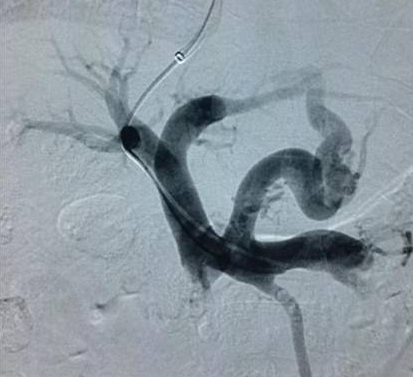

高飞教授与我科王立非主任联合完成了这例手术。TIPS之所以是“高大上”的介入手术,是因为医生手术时虽然只面对一个平面的屏幕,但要在肝内的肝静脉穿刺门静脉,必须要有全面的空间立体感,还要选好支架通道的路径。随着置入肝内支架的打开,门静脉血流瞬间被分流至腔静脉,一条“生命通道”搭建完成,患者门脉压力由术前38mmHg降至术后26mmHg。术后仅是在患者右侧颈部留下5mm大小穿刺口1个,术后患者无再出现呕血,术后7天复查CT显示术前明显迂曲增粗的食管胃底静脉已消失;现患者已康复出院。